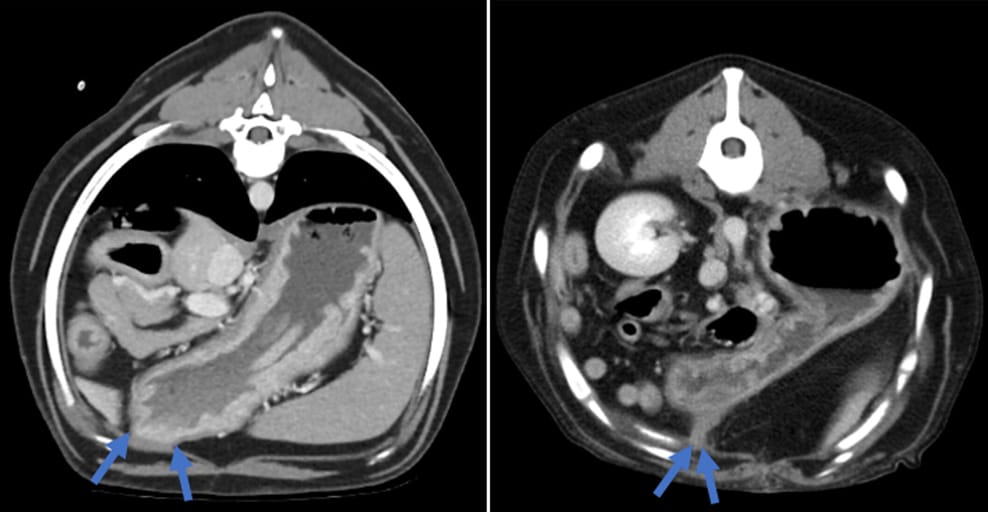

Post-contrast transverse CT images of the cranial abdomen at the level of the gastropexy site, displayed in a soft-tissue-window and illustrating a dog with a broad pedicle (left) and a dog with a narrow pedicle (right), marked by arrows.

CT findings showed a median gastropexy site attenuation of 38.5 HU and a mild thickening of both the gastric and body wall musculature. Neovascularization was present in 65% of cases, and 32% exhibited marked gastric dilatation. A gravel sign, indicative of delayed gastric emptying, was observed in 73% of cases. The non-anatomic group had narrower gastropexy pedicles, shorter gastropexy lengths, and more acute gastric angles compared to the anatomic group. Despite anatomical distortion, gastrointestinal clinical signs were not always present.